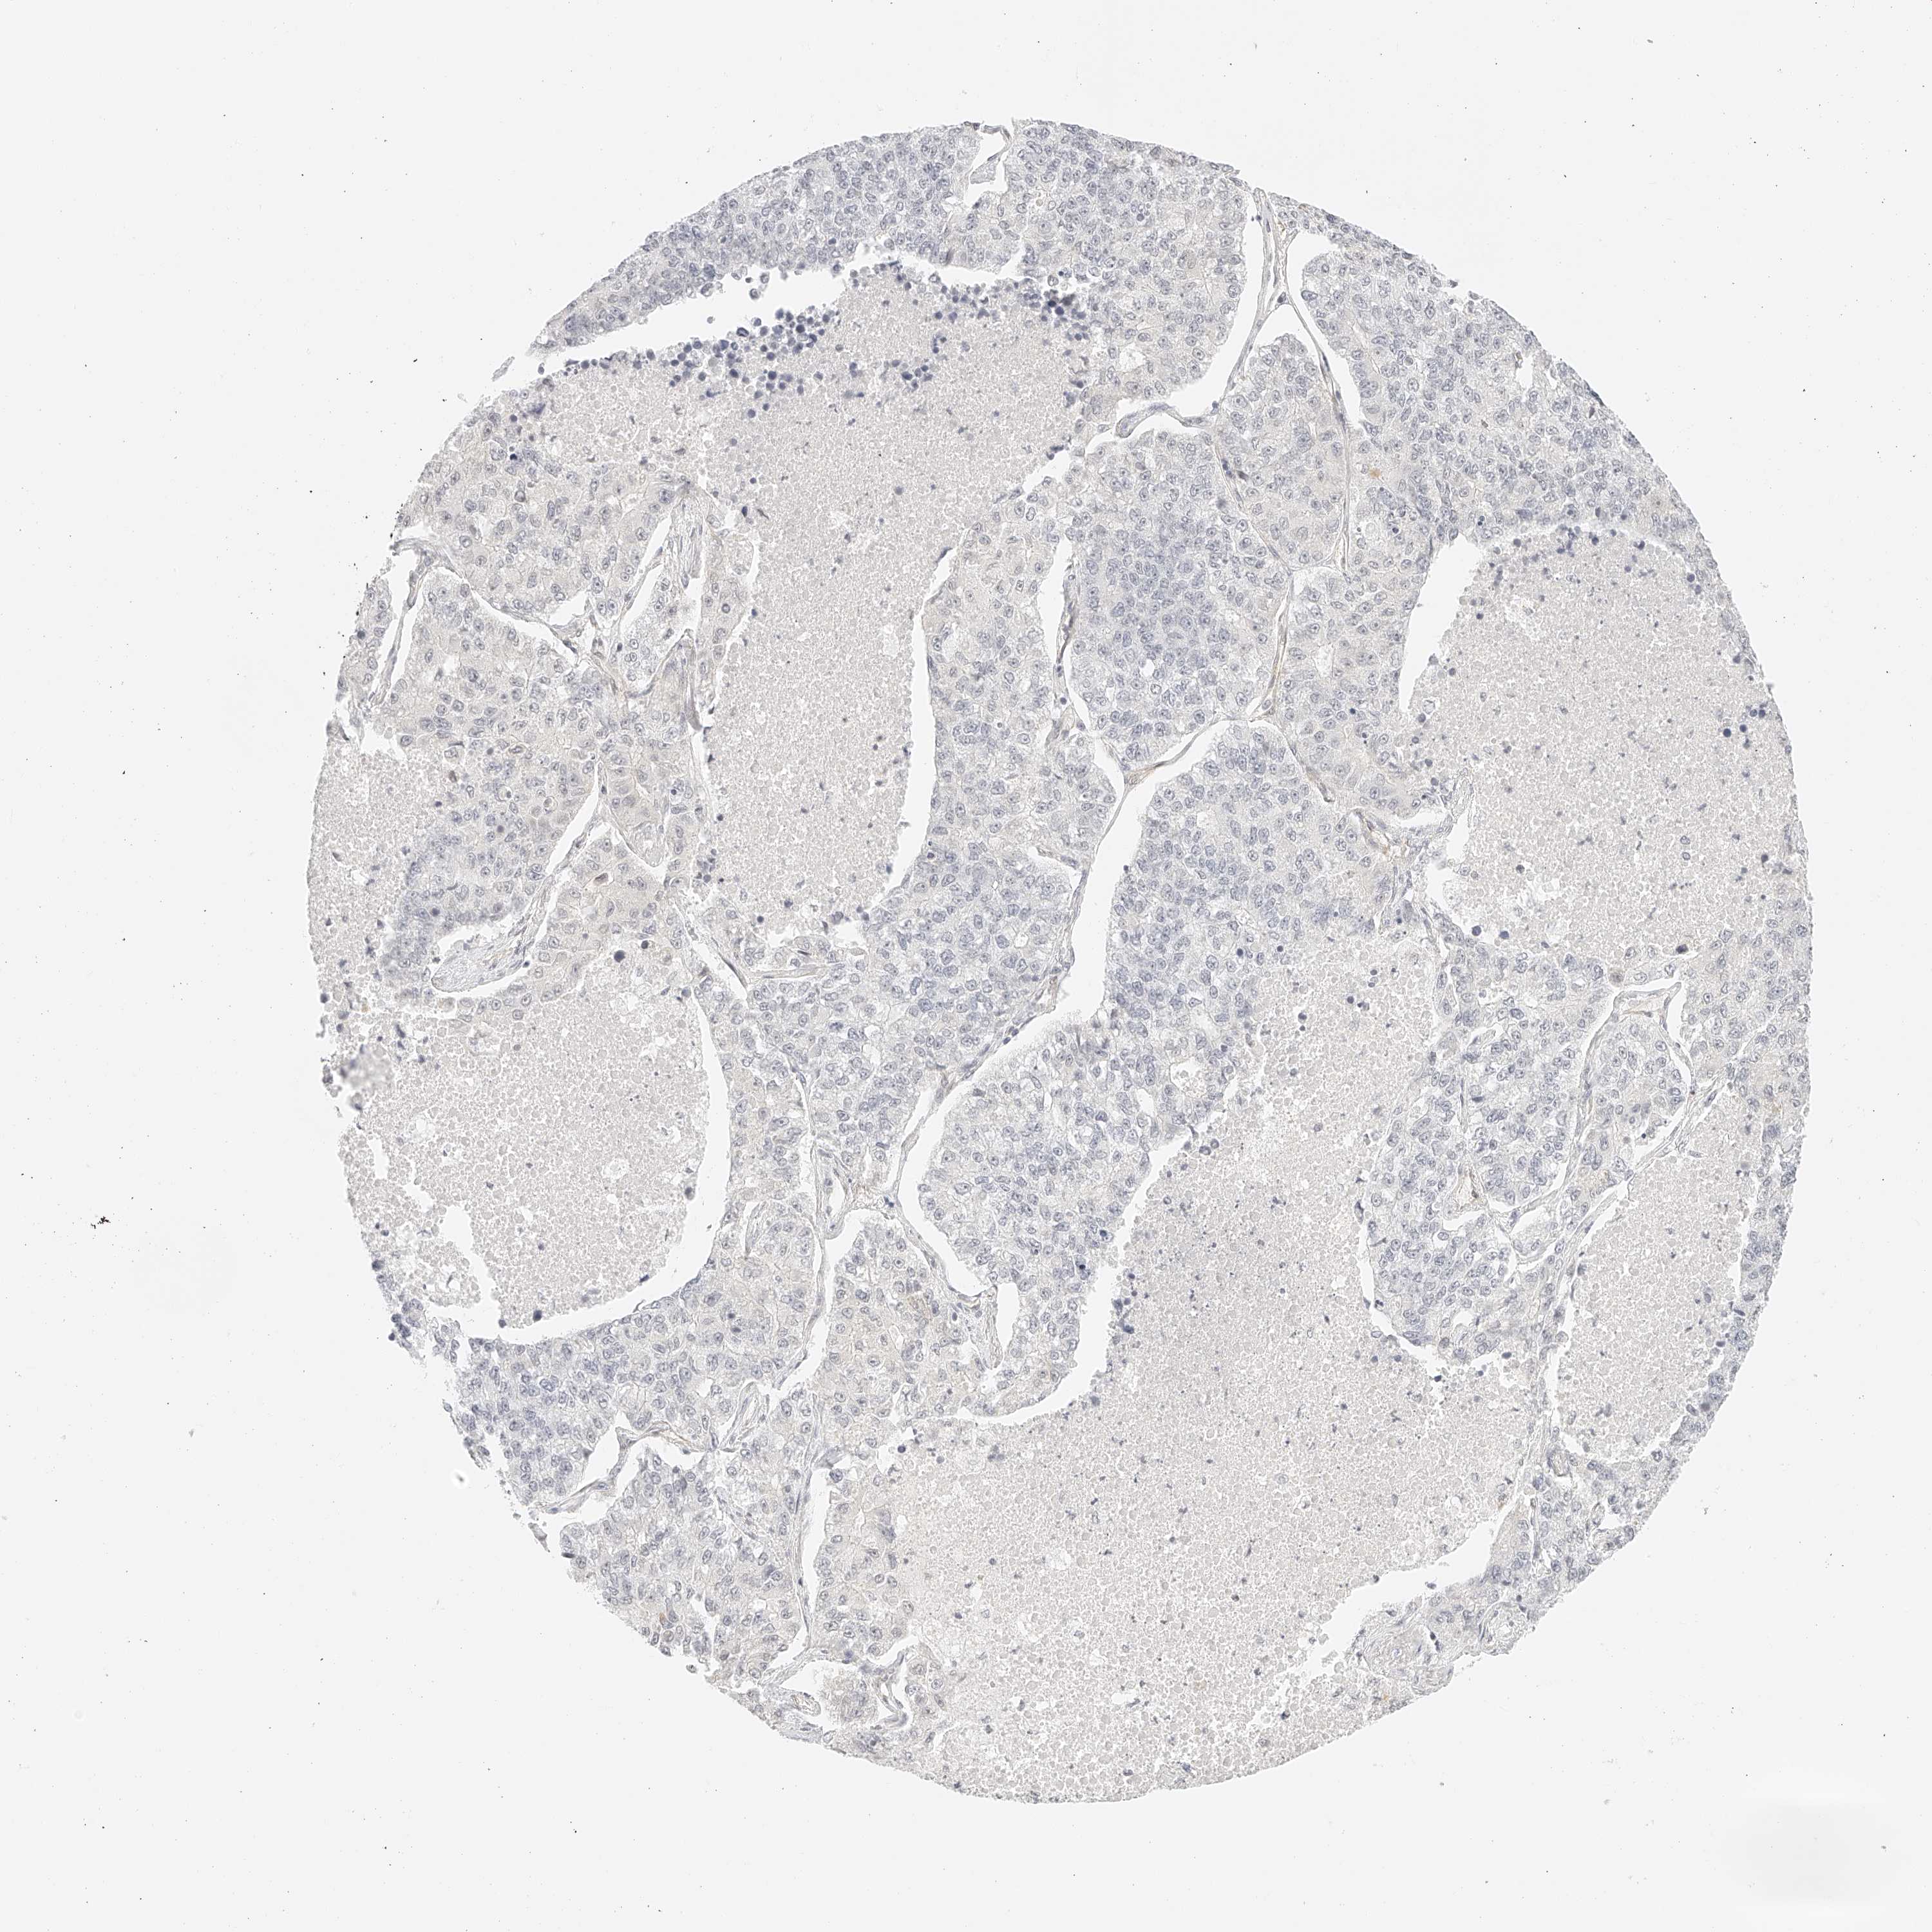

LUNG ADENOCARCINOMA (VALIDATION) - Interactive survival scatter ploti

The Survival Scatter plot shows the clinical status (i.e. dead or alive) for all individuals in the patient cohort, based on the same data that underlies the corresponding Kaplan-Meier plots. Patients that are alive at last time for follow-up are shown in blue and patients who have died during the study are shown in red.

The x-axis shows the expression levels (FPKM) of the investigated gene in the tumor tissue at the time of diagnosis. The y-axis shows the follow-up time after diagnosis (years). Both axes are complimented with kernel density curves demonstrating the data density over the axes. The top density plot shows the expression levels (FPKM) distribution among dead (red) and alive patients (blue). The right density plot shows the data density of the survived years of dead patients with high and low expression levels respectively, stratified using the cutoff indicated by the vertical dashed line through the Survival Scatter plot. This cutoff is automatically defined based on the FPKM cutoff that minimizes the p-score. The cutoff can be changed by dragging the vertical line or by entering a cutoff value in the square labeled "Current cut-off".

Under the Survival Scatter plot the p-score landscape (black curve; left axis) is shown together with dead median separation (red curve; right axis). Dead median separation is the difference in median mRNA expression between patients who have died with high and low expression, respectively. It is calculated as follows: median FPKM expression of dead patients with high expression - median FPKM expression of dead patients with low expression. This is intended to aid the user in visually exploring custom cutoffs and the associated p-scores and dead median separation.

Individual patient data is displayed and can be filtered by clicking on one or more of the category buttons on the top of the page. Categories describing expression level and patient information include: high, low, alive, dead, female, male and tumor stages. The scale of the x-axis can be toggled between linear and log-scale by clicking on the "x log" button. Mouse-over function shows TCGA ID, patient information and mRNA expression (FPKM) for each patient.

& Survival analysisi

Kaplan-Meier plots summarize results from analysis of correlation between mRNA expression level and patient survival. Patients were divided based on level of expression into one of the two groups "low" (under cut off) or "high" (over cut off). X-axis shows time for survival (years) and y-axis shows the probability of survival, where 1.0 corresponds to 100 percent.

ZFP69 is not prognostic in Lung Adenocarcinoma (validation)

: 2.84

Average pTPM 4.0

Number of samples 105